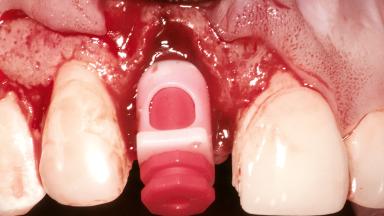

A healthy 26-year-old woman was referred for evaluation and treatment of her failing maxillary right central incisor (tooth 11). She reportedly traumatized the tooth at about age 9 and subsequently had repeated conventional and surgical endodontic procedures and fixed restorations. Despite these procedures, she had recurrent fistulas in the apical mucosa and a mid-facial pocket of 7 mm with suppuration. All other sites on the tooth probed 3 mm without inflammation. She presented with a medium biotype with triangularlyshaped teeth and a moderately high smile line, showing all of her papillas and a few millimeters of marginal gingiva in a full smile.Ceramic veneers were present on teeth 12, 21, and 22, and they were known to be somewhat bulky, eventually requiring replacement. She had a strong desire to avoid additional tooth preparation and would not consider a fixed dental prosthesis to replace tooth 11.